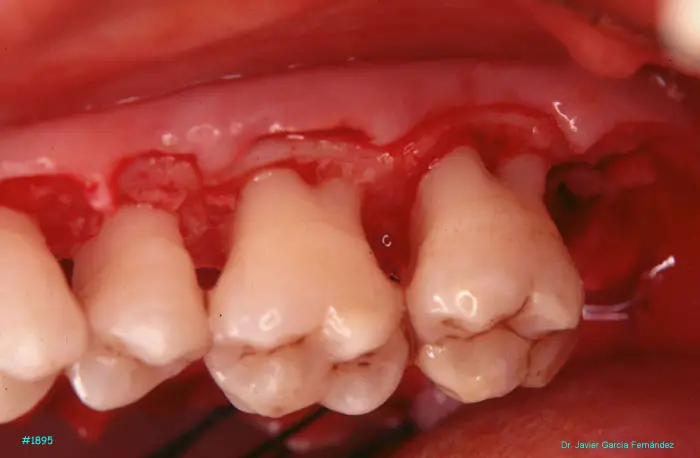

image 41